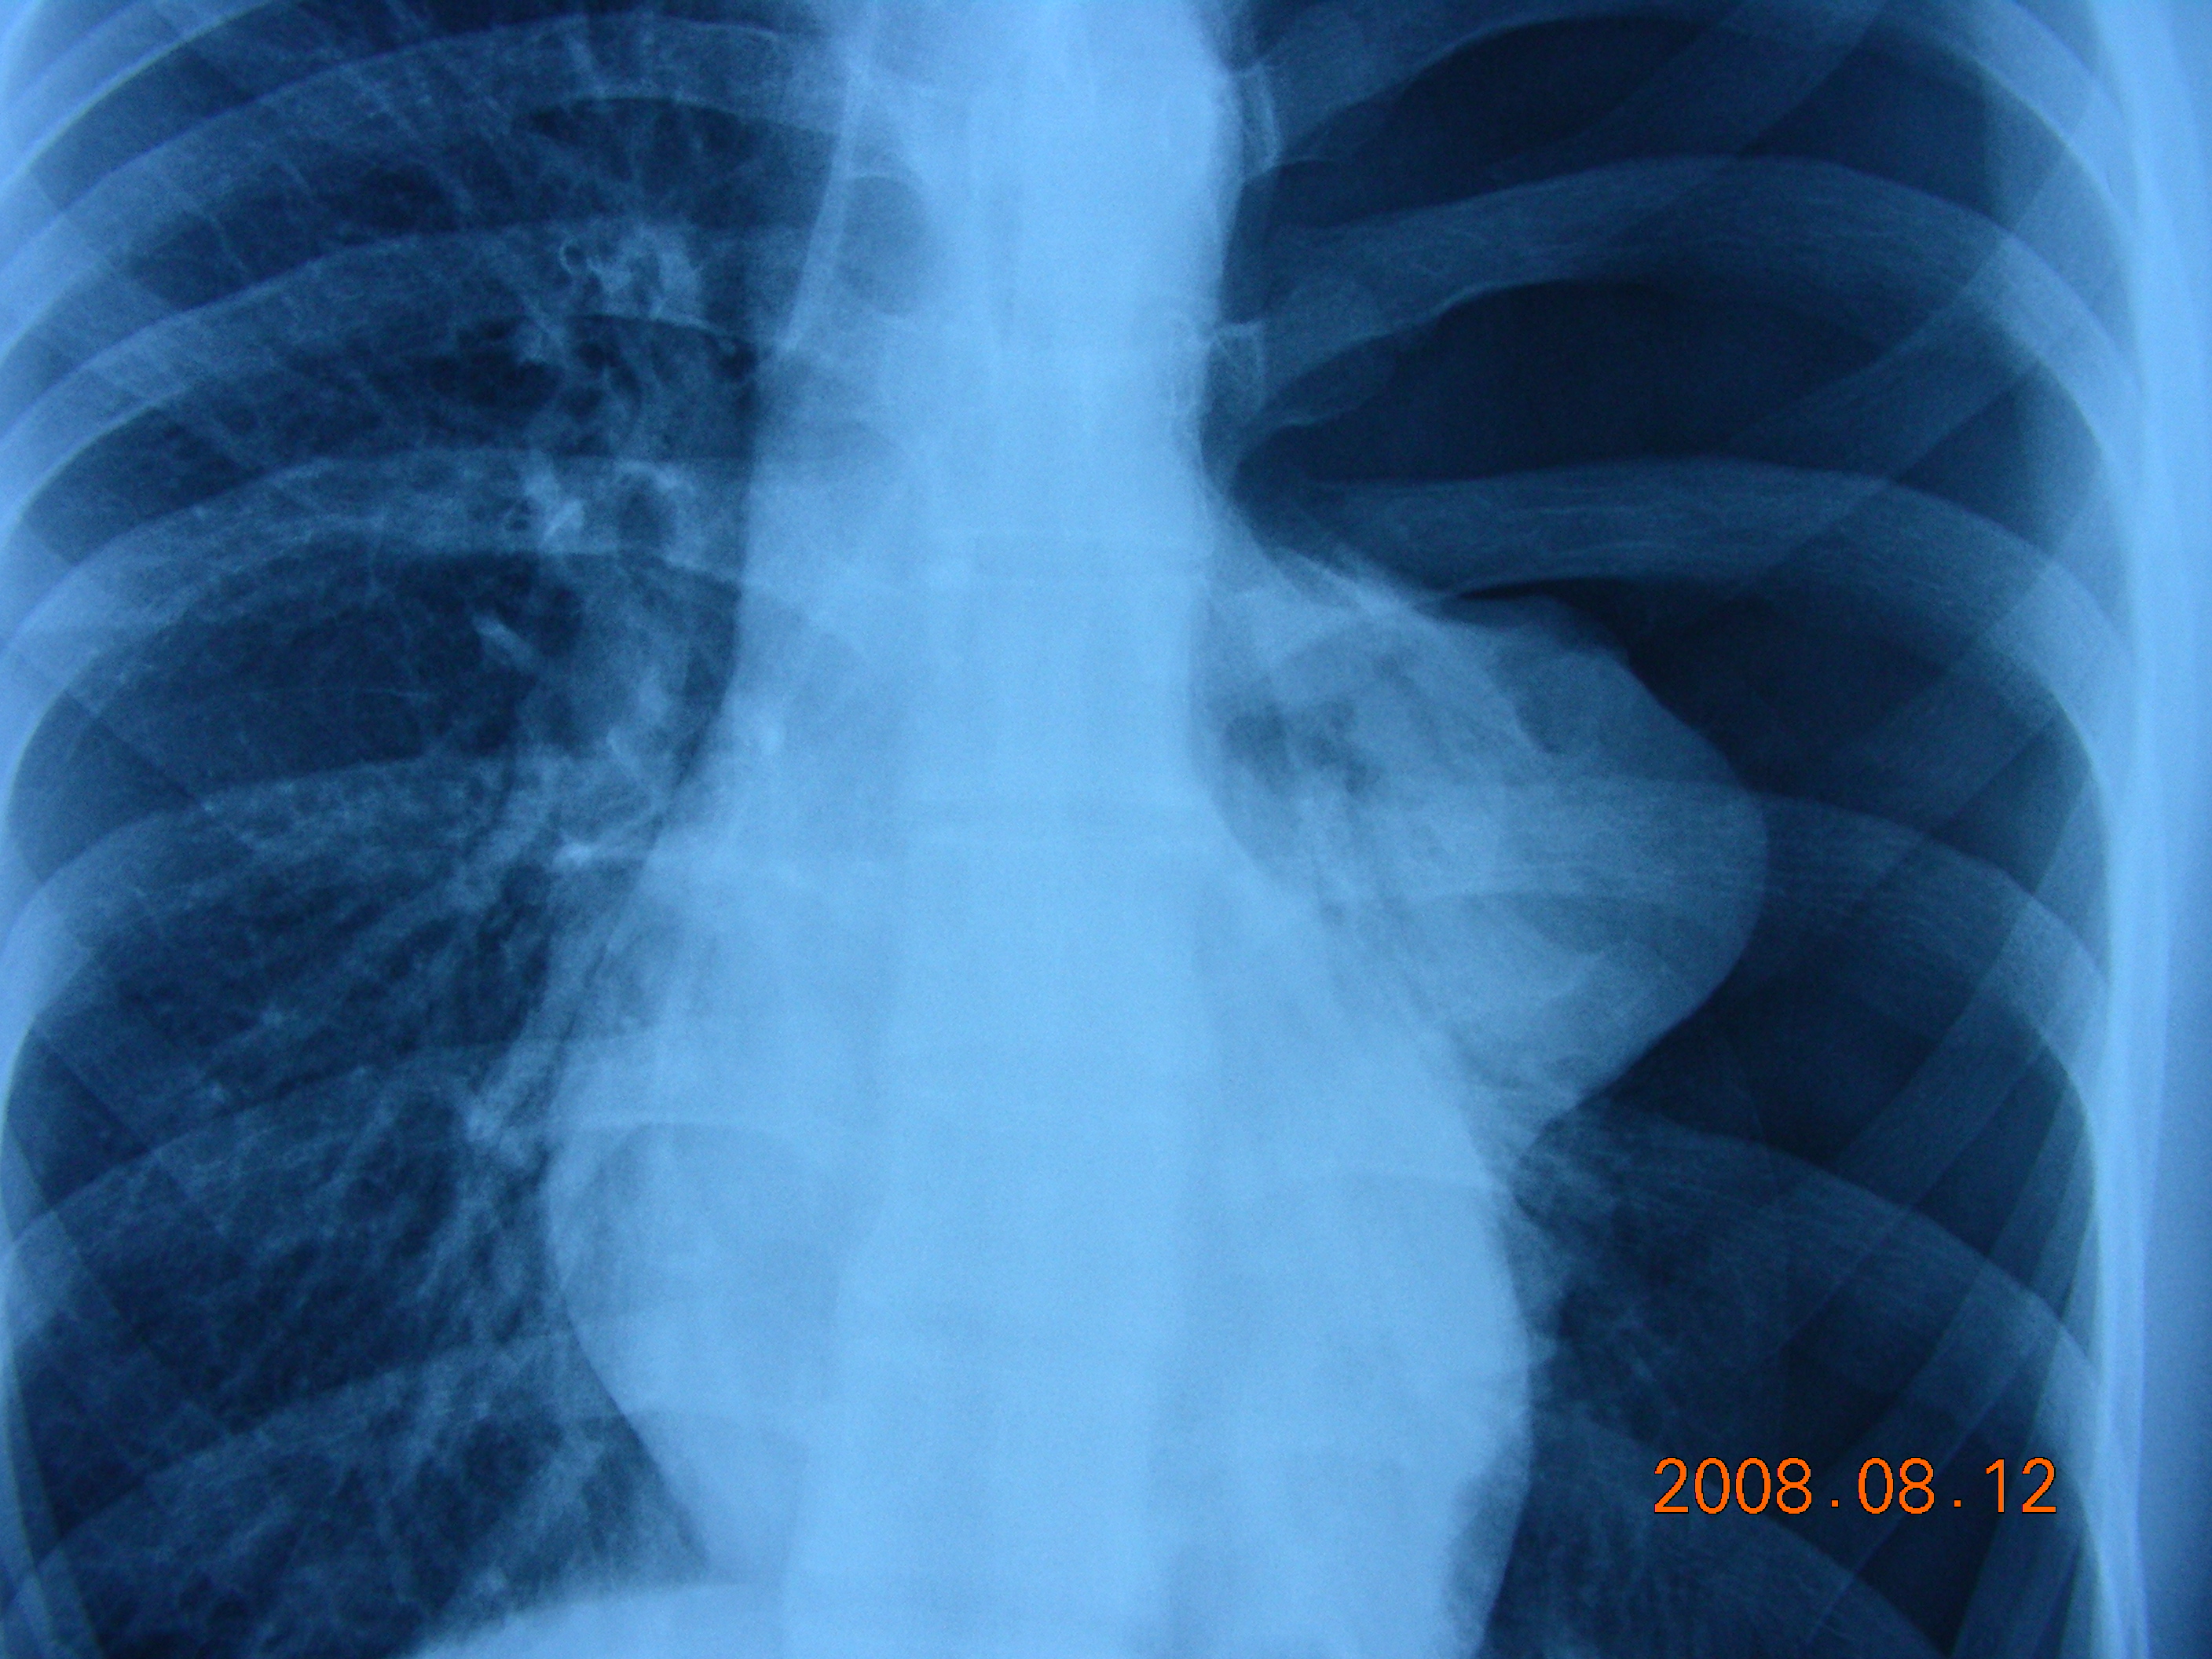

非创伤性脏层胸膜破裂而引起空气逸入胸膜腔称为自发性气胸。原发性气胸,又称恃发性气胸,指肺部常规X线检查未发现明显病变的“健康者”所发生的气胸。常见于20-40岁青壮年,瘦高体型男性较多。发生率大概8-10/100000,男多于女。 治疗:分为保守治疗(观察、胸腔闭式引流)和手术治疗。 保守治疗两年内平均可达25%以上,复发患者可达50%以。 手术目的:切除造成气胸的病灶并视情况性胸膜固定术,使气胸不致再发。 手术指征:①复发性气胸;②血气胸;③张力性气胸;④肺大泡明显者;⑤双侧气胸漏气严重、时间长,胸引效果不佳者;⑥居住地偏远;⑦工作性质特殊;⑧患者要求手术等等。 手术方式:胸部小切口或胸腔镜下行肺大泡切除、胸膜固定术。 (1)胸外科术前常规准备:血、尿常规,凝血II,肝肾功,免疫八项,血液生化检查;心电图,胸片检查等。 (2)向病人及家属交待病情和术中,术后可能发生的意外并行手术签字; (3)青霉素,普鲁卡因皮试试验,术前12小时禁食水。 3.手术当天可暂不进食,可经静脉输入糖、盐水、维生素等。 4.术后注意观察引流管是否通畅、引流液的颜色及引流量。 5.嘱患者深呼吸、咳嗽以促进气体的排出和肺的复张。